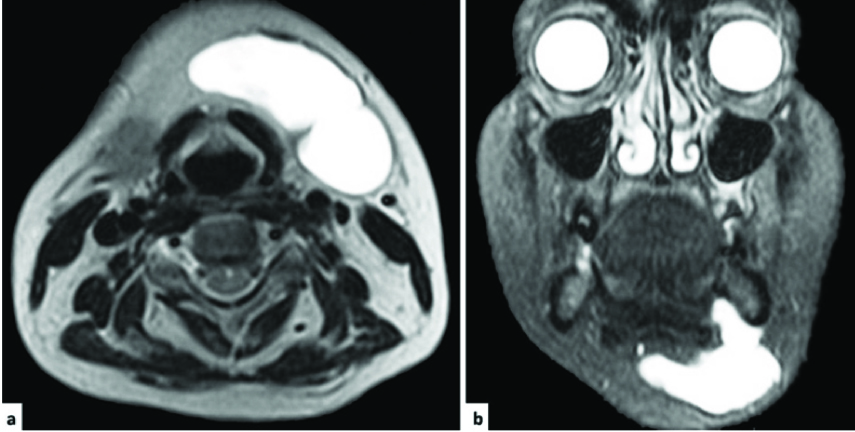

Ultrasonography was advised to study nature, size and extent of the lesion. The ultrasonogram (using 5-9 MHz linear probe) showed a hypoecogenic oval mass of 75x32 mm size, with thin wall and incomplete septae in the left submandibular region, suggestive of a benign cystic lesion [[Table/Fig-2]. Magnetic Resonance Imaging (MRI) showed well defined lobulated, round to oval lesion with smooth margins, measuring approximately 6x2.9x2.8 cm [Table/Fig-3a,b]. The lesion was present predominantly in the submandibular region on left side. Superiorly the lesion was extending upto the sublingual space on the left side superior to the mylohyoid muscle. Inferiorily it extended below the mylohyoid muscle, upto the level of superior margion of thyroid gland. Laterally, the lesion migrated till the platysma. However, no obvious extension through the platysma was seen. Medially the lesion was seen compressing the submandibular gland in its superior aspect and reaching upto the midline in its inferior aspect. MRI findings were suggestive of a well defined cystic lesion predominantly in submandibular space, having extensions into sublingual space [Table/Fig-3a,b].

Magnetic resonance imaging showing Plunging ranula (a) axial (b) coronal section